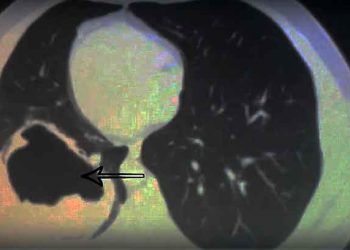

Read moreDetailsVirchow Hidatit, akciğer alveollerinin aşırı genişlemesine denir. Diğer bir anlam olarak da konak dokularında infiltrasyonla sonuçlanan çok sayıda dış tomurcuklanmanın...